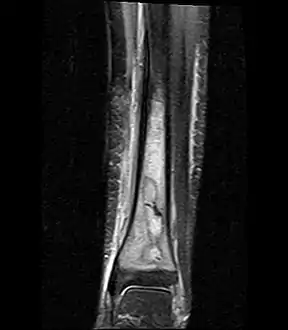

Fat saturated STIR (short tau inversion recovery) image showing hyperintense edema in the calf musculature, marrow edema, and subperiosteal pus. The intramedullary abscess cavity is hyperintense as well.

Coronal fat suppressed STIR image showing, bone marrow and subcutaneous edema as well as subperiosteal edema. The thin hypointense rim surrounding the intramedullary collection represents the reactive interface between the abscess and the body's attempt to wall it off.